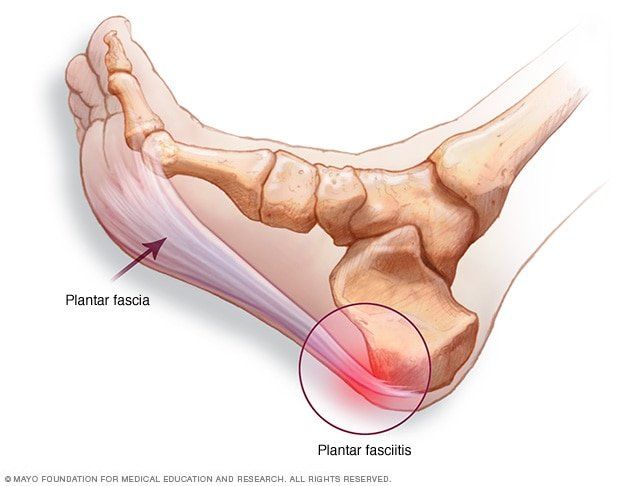

Located on the sole of the foot, which runs from the toes to the heel is a thick, fibrous band of tissue known as the plantar fascia and in some instances can become irritated. There are a number of muscles that act around the ankle joint to help perform the available movements, these include: